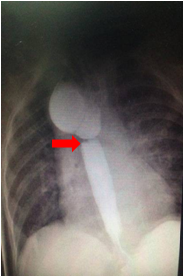

2.颈、胸、腹正侧位X线摄片示导管卷曲或造影显示食道近端盲袋。

吻合口狭窄